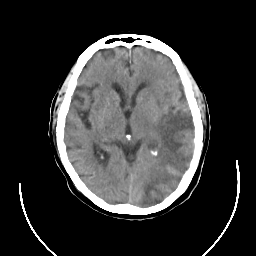

CT Study #3 -- Slice #13

[Home][Help][Clinical][Tour 1] Slice 13